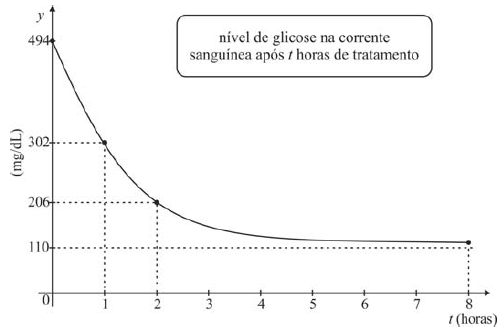

Com alto nível de glicose, medida em mg/dL, um paciente apresentou, na corrente sanguínea, após tratamento, a resposta descrita no gráfico abaixo, em que t é dado em horas e t = 0 corresponde ao tempo da primeira medição e ao início do tratamento.

Considere que o gráfico do nível de glicose descreva o comportamento da função !$ G(t) = a + \dfrac{b}{2^{(t+1)}} !$ , em que a e b são constantes reais positivas. Nessa situação, considerando os valores de G(0) e G(1), verifica-se que a soma do valor de a com o valor de b é

Com alto nível de glicose, medida em mg/dL, um paciente apresentou, na corrente sanguínea, após tratamento, a resposta descrita no gráfico abaixo, em que t é dado em horas e t = 0 corresponde ao tempo da primeira medição e ao início do tratamento.

Com base na situação hipotética e no gráfico apresentados acima, assinale a opção correta.